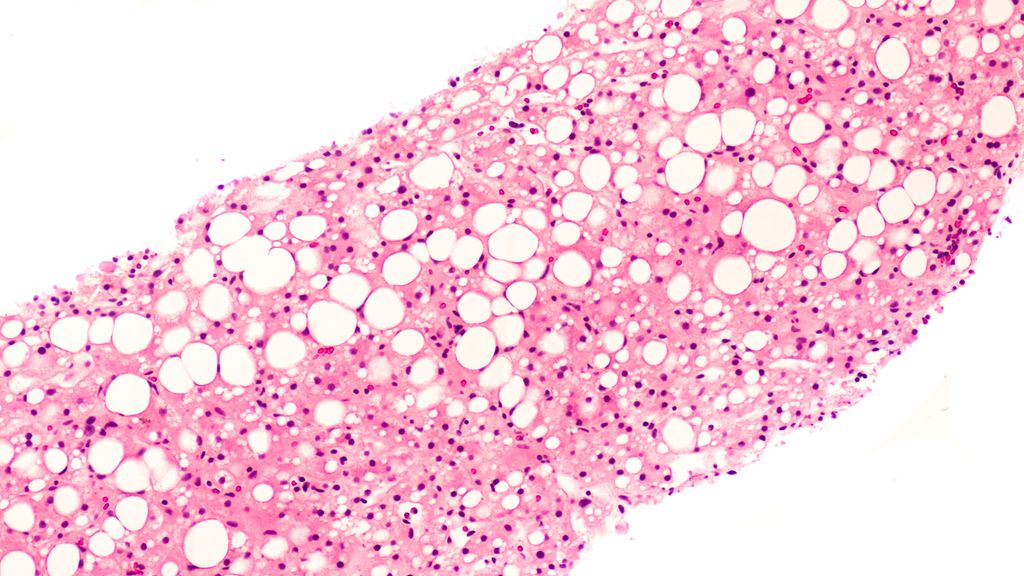

Chez les patient·es à faible risqueatteint·es de syndromes myélodysplasiques (SMD), l’anémie nécessitant des transfusions constitue souvent le principal problème altérant la qualité de ...

Après une autogreffe de cellules souches, le traitement d’entretien par lénalidomide constitue le standard chez les patient·es atteint·es d’un myélome multiple nouvellement diagnostiqué ...